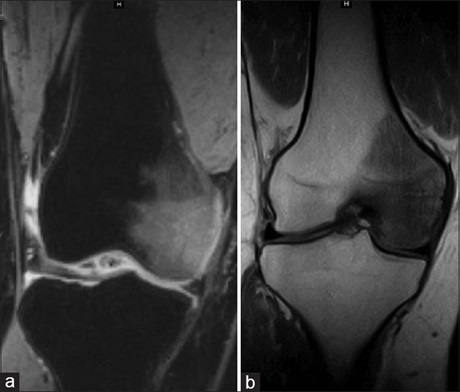

Regional migratory osteoporosis (RMO) is an uncommon disorder that predominantly affects middle-aged males, presenting as

migrating arthralgia involving the lower extremities. It is a transient condition that involves joints without preexisting disease and

resolves spontaneously without long‑term sequelae. We describe serial imaging findings in a patient with RMO followed over a period

using various imaging modalities which showed typical migrating osteopenia involving the knee, ankle, and foot.